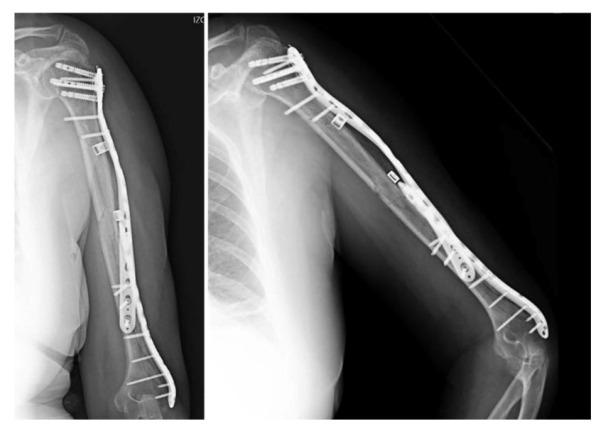

: Non-prosthetic peri-implant fractures (NPPIFs) are rare injuries occurring around internal fixation devices, and are distinct from periprosthetic fractures. While most studies focus on the femur, humeral NPPIFs remain poorly documented. This case illustrates a complex humeral NPPIF and highlights key surgical considerations. : A 62-year-old woman presented with a spiral humeral shaft fracture (AO 12B2) after a fall. Following closed reduction and antegrade intramedullary nailing, an intraoperative peri-implant fracture occurred at the distal interlocking screw. CT imaging revealed a complex fracture extending from the lateral condyle to the proximal humerus. Treatment included implant removal and open reduction with dual plate fixation-lateral distal and helically contoured proximal plates-plus cerclage bands and antibiotic-loaded beads. Recovery was uneventful, with a full range of motion achieved at six months. At one year, the DASH score and MEPS were 86 and 75, respectively. : Humeral NPPIFs are challenging and require individualized, biomechanically sound strategies. This case reinforces the importance of intraoperative assessment and careful implant selection in humeral fracture management.

非假体周围植入物骨折(NPPIFs)是发生在内固定装置周围的罕见损伤,与假体周围骨折不同。虽然大多数研究集中在股骨,但肱骨NPPIFs的文献记载仍然很少。本病例说明了一例复杂的肱骨NPPIFs,并强调了关键的手术注意事项。一名62岁女性在跌倒后出现肱骨干螺旋骨折(AO 12B2)。在进行闭合复位和顺行髓内钉固定后,术中在远端锁定螺钉处发生了植入物周围骨折。CT成像显示骨折复杂,从外侧髁延伸至肱骨近端。治疗包括取出植入物,采用双钢板固定(外侧远端钢板和螺旋形近端钢板)、环扎带和载抗生素骨珠进行切开复位。恢复过程顺利,六个月时实现了全范围活动。一年时,DASH评分和MEPS分别为86和75。肱骨NPPIFs具有挑战性,需要个体化的、生物力学合理的策略。本病例强化了术中评估和在肱骨骨折治疗中谨慎选择植入物的重要性。